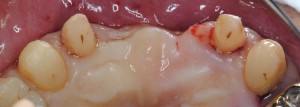

上顎前歯2本欠損 ブリッジの予定だが・・・

ブリッジの支えになる歯が歯周病なので歯周外科を行った。歯肉に隠れていた歯根表面に歯石が見える(矢印)。